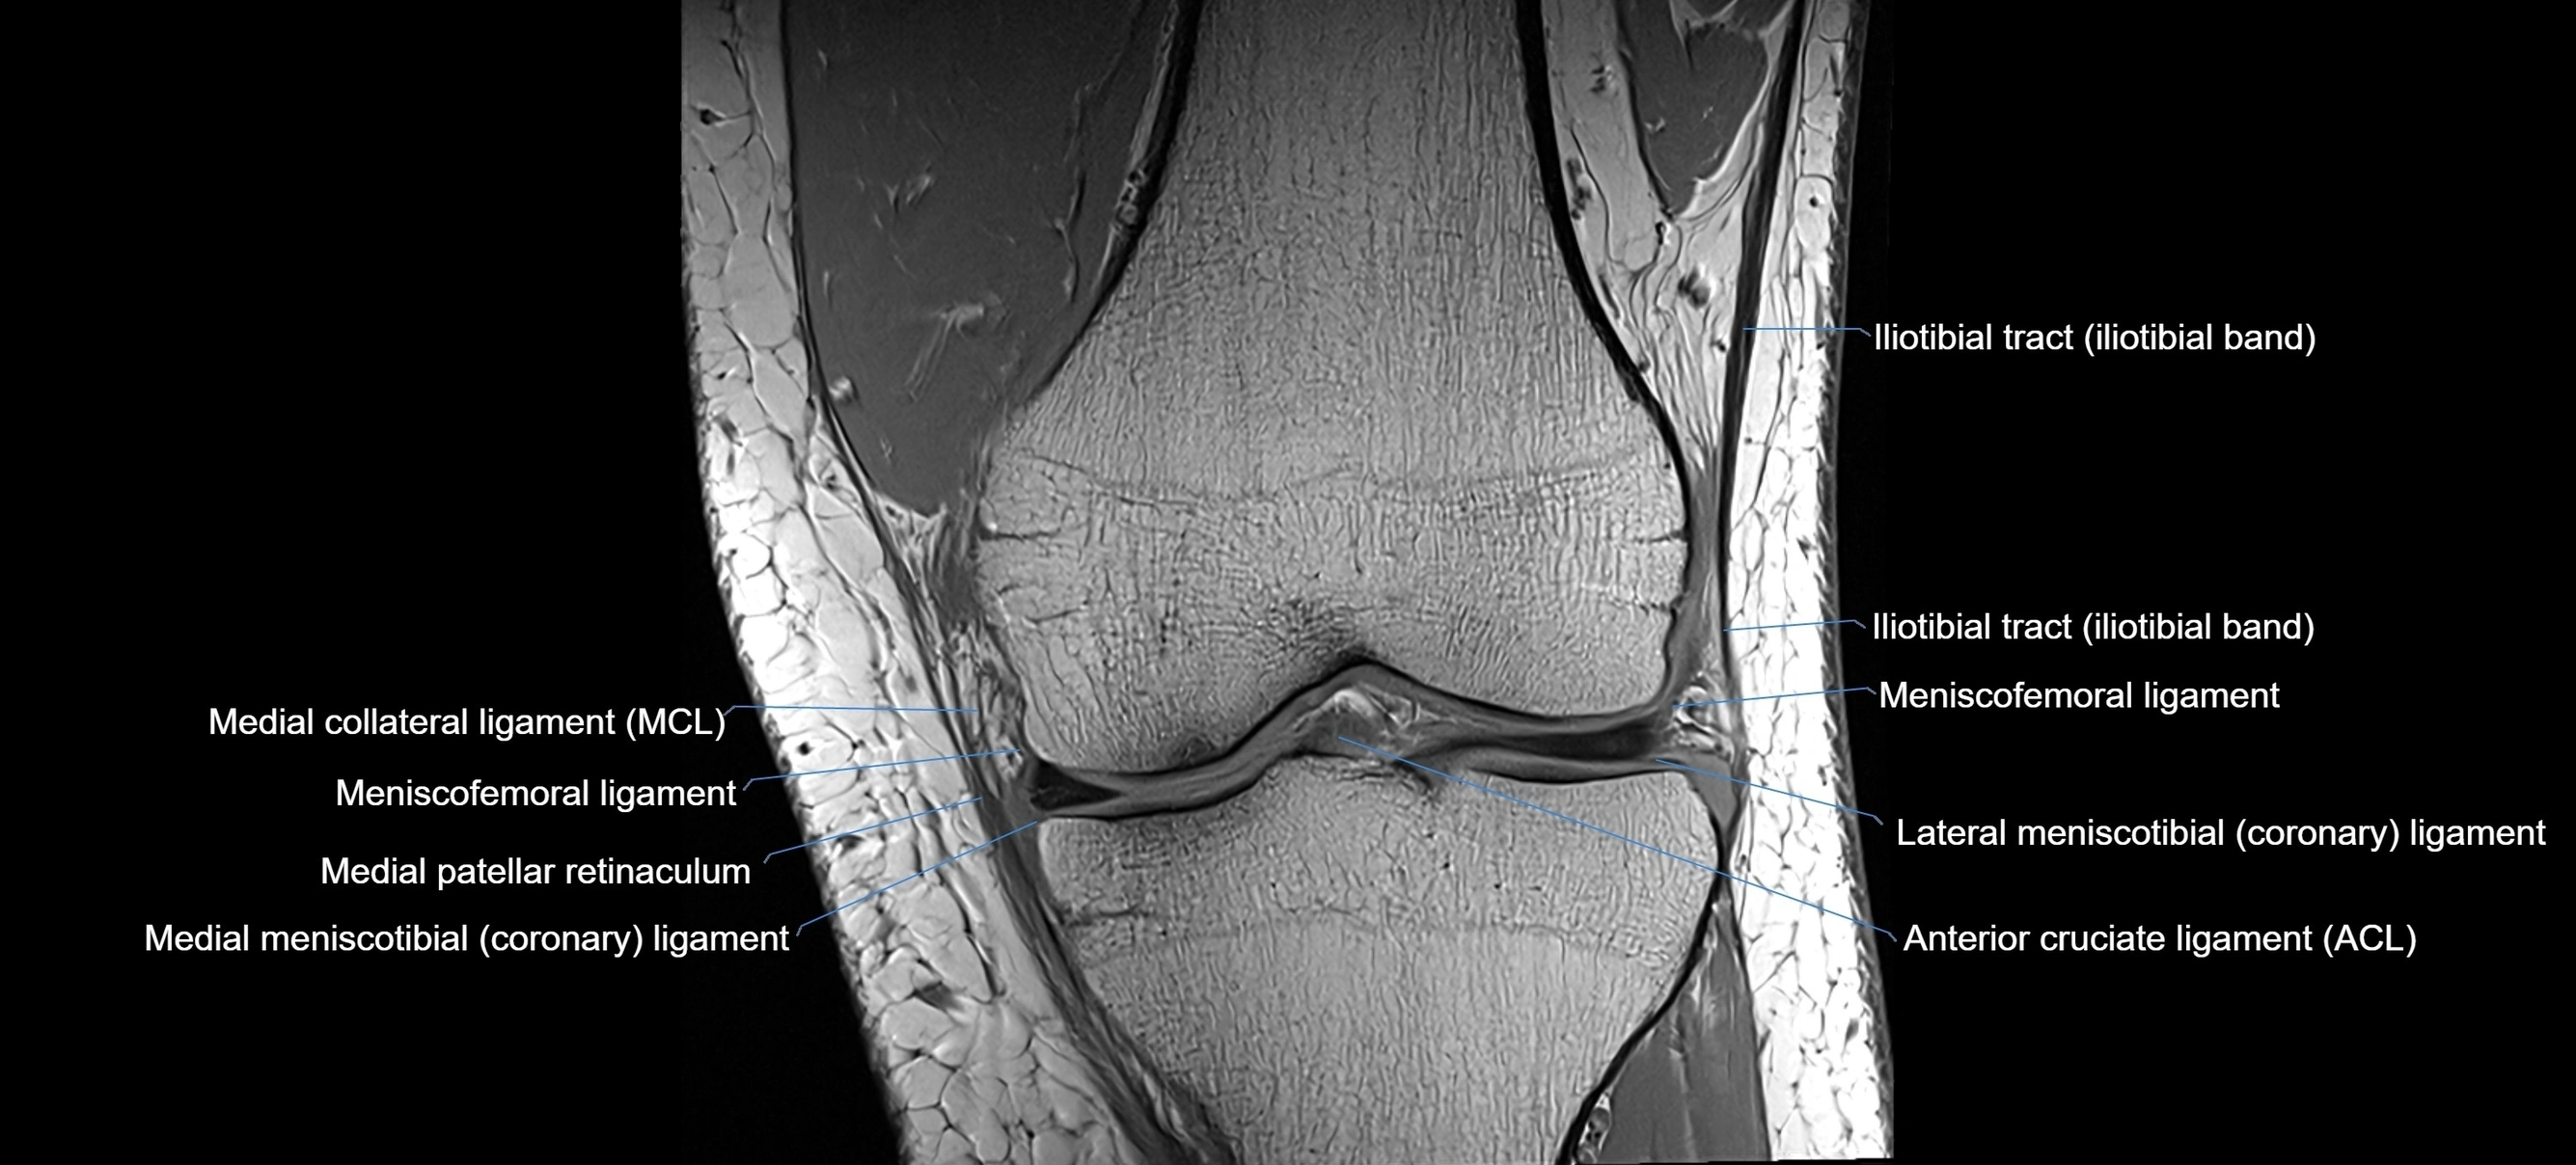

MRI images

image